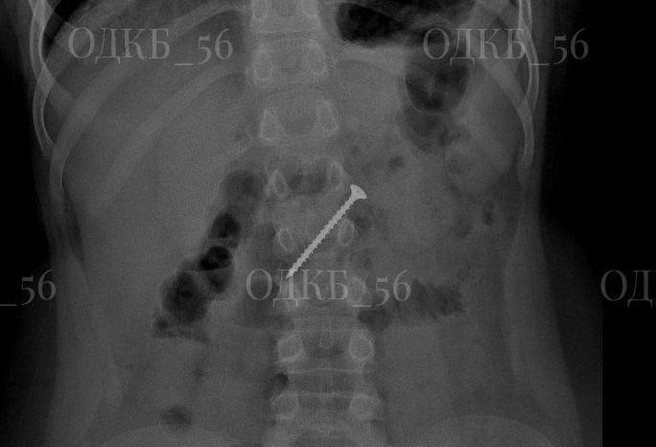

В Оренбургскую областную детскую клиническую больницу из одного из районов региона доставили 9-летнего школьника с не самой стандартной жалобой — его родители заподозрили, что он случайно проглотил… 5-сантиметровый саморез. Как именно и, главное, зачем — неизвестно, но факт есть факт — обследование подтвердило, что в желудке есть инородное тело.

Мальчика доставили в приемное отделение ОДКБ по направлению из ЦРБ уже с результатами рентгенографии брюшной полости. Команда медиков экстренно провела ему общее обезболивание и сделала эндоскопию верхнего отдела ЖКТ. Саморез находился в двенадцатиперстной кишке, и представлял неиллюзорную угрозу развития кишечной непроходимости и пробивания кишки.